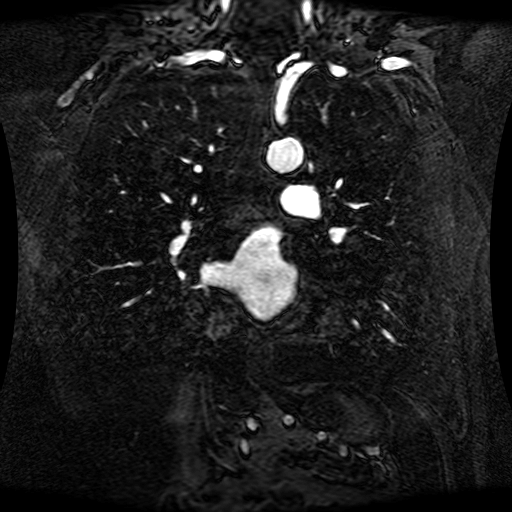

Data Description

These magnetic resonance angiography (MRA) images show coronal slices acquired from consecutive anteroposterior positions within the torso. The study was performed on a 1.5T General Electric (GE) Signa imaging system with gadolinium-contrast-enhancement for visualization of the cardiopulmonary vasculature. The pulse sequence used was a 3D time-of-flight fast spoiled gradient recalled acquisition in steady state (FSPGR, TR=6.3, TE=1.4, NEX=1, FOV = 40cm, slice thickness = 1.2mm).

This sample image contains 76 frames. It is available in DICOM format (E1154S7I.dcm), as an animated GIF (E1154S7I.gif), as .ogg, .mp4, .webm, and .swf animations (one of which is shown above), or as individual PNG-format frames (see below).